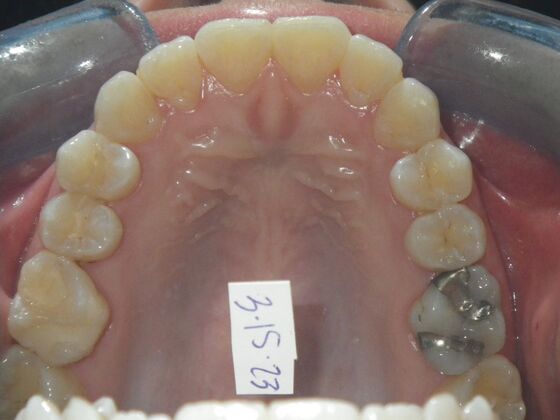

This patient had concerns with the lower anterior teeth. There were some slight rotations and the midline of the lower incisors wasn't lined up with the upper midline. To correct this we used slenderizing of teeth in strategic areas of the lower arch to correct the rotations and line up the midlines. Patient very pleased with the results.